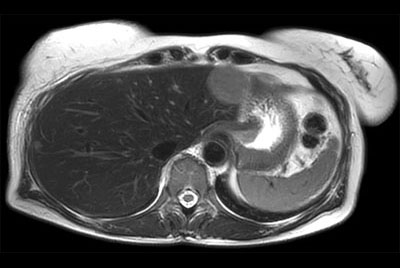

Liver metastasis